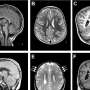

How errors in the cytoskeleton lead to a smaller brain

Why do some children develop a brain that is too small (microcephaly)? An international research team involving the German Primate Center—Leibniz Institute for Primate Research (DPZ), Hannover Medical School (MHH), and the Max Planck Institute of Molecular Cell Biology and Genetics has used human brain organoids to investigate how changes in important structural proteins in […]